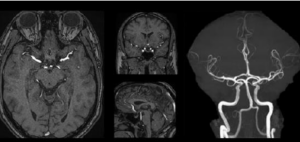

The DAISI project focuses on the development of an artificial intelligence solution integrated into the workflow to assist in the detection, orientation and follow-up of unruptured intracranial aneurysms on MRI. Intracranial aneurysm is a not rare arterial pathology (3%), asymptomatic except for complications, and difficult to diagnose on cerebral MRI performed for another indication.

Intracranial Aneurysm